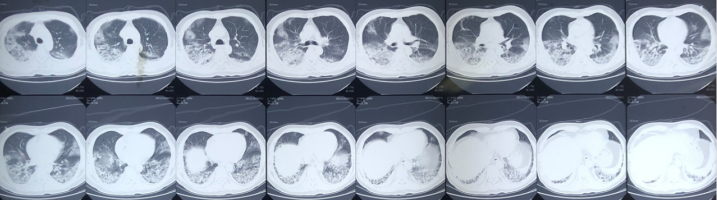

影像学变化

经过治疗,患者双肺磨玻璃样改变较前有所吸收,12月6日随访CT可见双肺间质性改变较前明显改善(图6)

图片

6  患者影像学变化